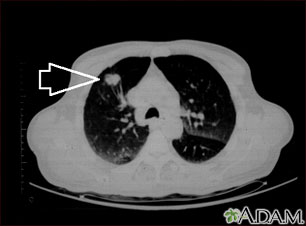

- When a tumor or mass (clump of cells) is suspected, including a solitary pulmonary nodule seen on a chest x-ray

- Lung cancer or cancer that has spread to the lungs from elsewhere in the body

- Tumors, nodules, or cysts in the chest